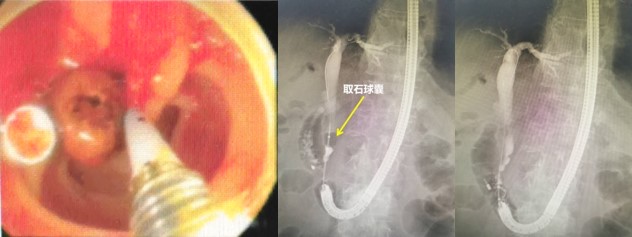

赵刚副主任凭借丰富的经验和精湛的技术,运用胃镜佩戴透明帽顺利找到前期设定的钛夹标记及十二指肠主乳头,然后利用专业器械,在内镜精细操作下,成功进行乳头括约肌切开及球囊扩张术,并最终将胆管内结石顺利取出。整个操作用时不到20分钟。

毕Ⅱ式胃大部切除术后的ERCP操作难度比普通ERCP超出很多,首先就是内镜的选择,按照《中国ERCP指南(2018版)》的建议,推荐首选十二指肠镜进行操作,但十二指肠镜在进镜操作以及寻找输入袢和十二指肠乳头方面明显不如直视镜。消化内科团队通过前期数年来的工作积累,制定了毕Ⅱ式胃大部切除术后ERCP操作的“交大二附院流程”,那就是先进行胃镜检查,由操作者亲自确认术式、输入袢肠管的走行以及十二指肠主乳头的位置,同时在内镜下对乳头进行定位标记,另外,对于输入袢开口较为隐蔽或内镜通过输入袢口较为困难的病例,操作者也会在输入袢口处额外进行标记,以便于后续ERCP操作时的二次寻找。在手术操作过程中,消化内科ERCP团队一般都会选用胃镜佩戴透明帽进行操作,透明帽一方面有利于进镜寻找目标肠袢,另一方面也可提高乳头插管时的镜身稳定性。